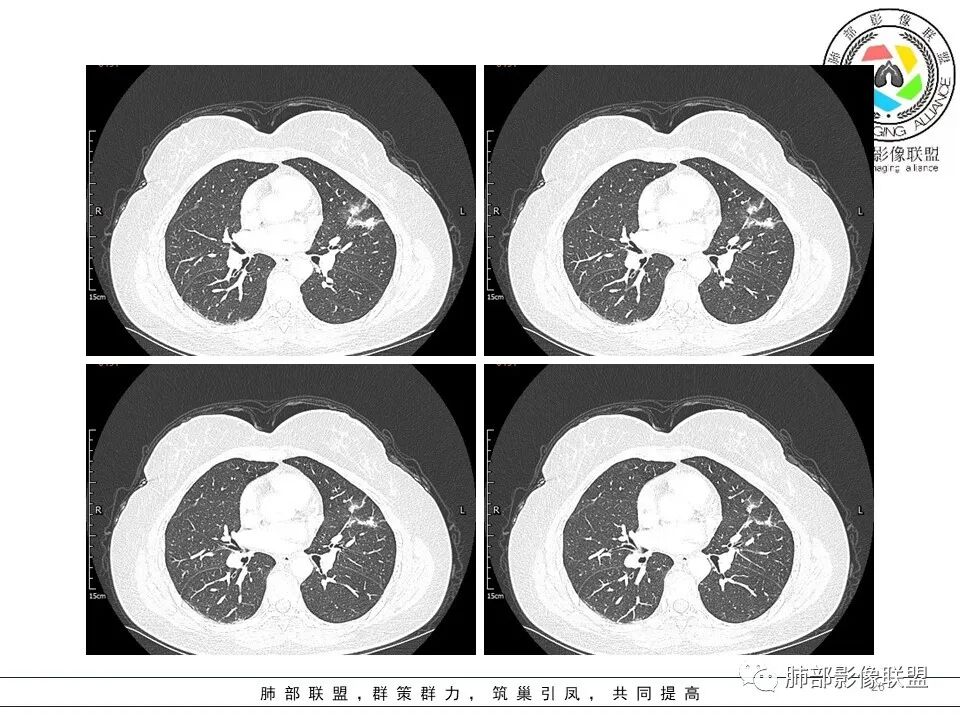

左肺上叶近胸膜下磨玻璃小结节,考虑早期腺癌,大结节感觉密度混杂,考虑良性感染

左肺上叶ggo,短毛刺,空泡征,6个月后复查病灶似变大,有轻度不均质强化,腺癌?胸膜下粟粒结节,无变化,良性?

中年女性,发现肺部结节半年,CT左肺上叶磨实混合型结节影,有膨隆,有凹陷,有毛刺,不均匀轻度强化,考虑腺癌可能,鉴别炎肌母

左肺上叶舌段mGGO,实变区可见支气管充气征直达远端并扩张,实变区膨胀与收缩共存,增强轻度强化,血管漂浮,未见受侵,纵隔内未见肿大淋巴结,中年女性,慢性病程,症状逍遥,半年复查病灶增大,倾向恶性病变,高度怀疑MALT。

左上肺实性占位,部分磨玻璃样改变,多发细小毛刺,胸膜牵拉,临近病灶血管增粗,病灶内见支气管,考虑恶性可能性大。鉴别肉芽肿性炎(病灶太散了,病灶中间见正常肺组织,感觉不符合)。

左肺上叶胸膜下结节,边缘可见毛刺及长索条,内可见支气管影略扩张,周围可见片状磨玻璃,增强后呈不均匀强化,内血管略增粗,复查大小没有变化,考虑腺癌。

短毛刺,空泡蜂窝,肺腺癌,靠近胸膜结节太小,性质待定。

中年女性,左肺上叶混合ggo,边界清晰,边缘分叶,内见空泡,短毛刺,血管穿行,胸膜牵拉,增强轻中度强化,考虑腺癌iac。鉴别支气管扩张,扭曲,淋巴瘤

左肺上叶胸膜下实性结节,周围散在磨玻璃结节,边缘收缩,胸膜牵拉,形态不规则,有分叶,毛刺,兔耳征,内部可见多个小空泡,平扫密实尚均匀,增强后不均匀强化,内部可见低密度坏死,血管束穿行,考虑恶性:浸润性腺癌,鉴别炎性肉芽肿。

左肺上叶胸膜下混合密度结节影,其内可见小空泡、扩张支气管,边缘短毛刺、微分叶,周围磨玻璃影,边界清。复查实性成分增多,结节增大,不均匀强化,可见低密度坏死,考虑恶性,腺癌可能

左肺上叶见磨玻璃结节影,部分实变,边缘不规则,可见长短不一毛刺,分叶及胸膜牵拉,病灶内见支气管走形,增强扫描,病灶实变区轻度强化,似见坏死区,考虑腺癌可能。

左肺上叶实性结节分叶短毛刺、细支气管轻度扩张并空泡、周围不规则分叶边界清楚GGO,半年后复查,目测大小没有明显变化,其内的考虑细支气管扩张及空泡变小,说明病灶仍在发展,与胸膜相连,但胸膜凹陷不明显,总体考虑恶性可能,腺癌或粘液腺癌可能,

左肺上叶混合磨玻璃结节,周围可见毛刺,胸膜牵拉,病灶内血管增粗,支气管略扩张,收缩力较大。考虑中分化腺癌;鉴别主要还是感染。

左肺上叶胸膜下混合密度结节影,部分边缘可见磨玻璃,其内可见小空泡,边缘短毛刺、微分叶,不均匀强化,可见低密度坏死,考虑恶性,浸润性腺癌

左肺上叶胸膜下混合磨玻璃结节,实性为主,周围磨玻璃清晰,小空泡,血管进入无破坏,短毛刺,半年复查实性区似稍增大,考虑恶性,腺癌IAC,读片带个尾巴,淋巴瘤代排